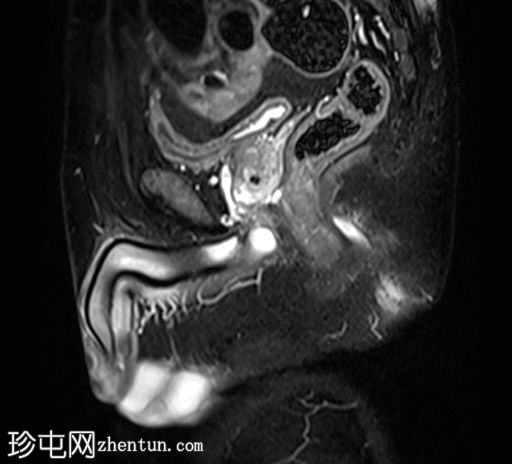

7.jpg

冠状位T1

脂肪饱和度

位于5点钟和6点钟位置之间,在STIR和T2加权图像上呈高信号。

瘘管起源于括约肌间平面附近,穿过肛门内外括约肌,并延伸至左侧坐骨肛门窝。瘘管内充满液体信号,周围有轻微水肿。肛提肌上方未观察到颅骨延伸。

根据圣詹姆斯大学医院的磁共振分类系统,该病例被归类为III级左侧肛周经括约肌瘘,左侧坐骨肛门窝可见炎症改变。